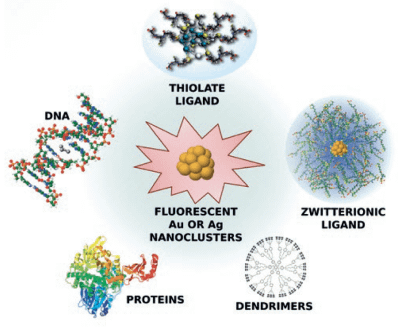

- Biosensorics with superior detection is based on metallic nanoclusters stabilized by biomolecules (new class of non-linear fluorophores) which allow deep tissue penetration and direct imaging of living cells for early medical diagnostics

- Experimental part: Dr. Rodolphe Antoine and Dr. Philippe Dugourd (Université Claude Bernard Lyon 1, CNRS, Lyon, France)

IF Application of new nanostructured materials in medical diagnostics

In order to improve the specificity and the sensitivity of the technique, nanocluster probes are under development to replace theses cy-hydrazide dyes.